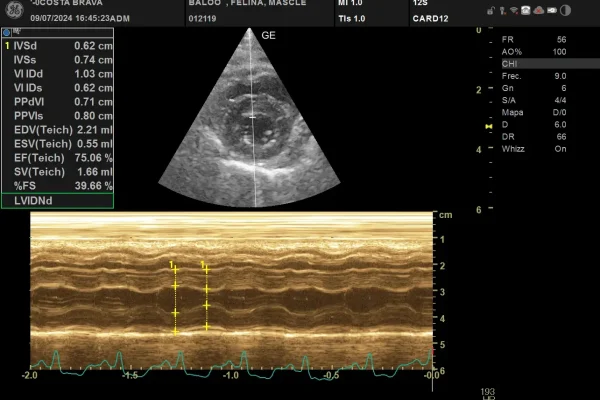

En Baloo es va presentar amb una quadre de distrés agut per una insuficiència cardíaca congestiva. L’ecografia mostrava un fenotip hipertròfic amb disfunció diastòlica. Els nivells de troponina I es trobaven a 11,2 (rang de referència 0-0.06) .

Mode M. Tall transversal del ventricle esquerre. S’observa un gruix diastòlic anormal tant en paret septal com lliure del ventricle esquerre (hipertròfia a partir de 0,6cm).